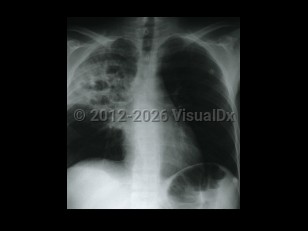

Chest pain, Pleural effusion, 50-59 year old Female

TuberculosisTuberculosis

Lung abscess

Malignant mesothelioma